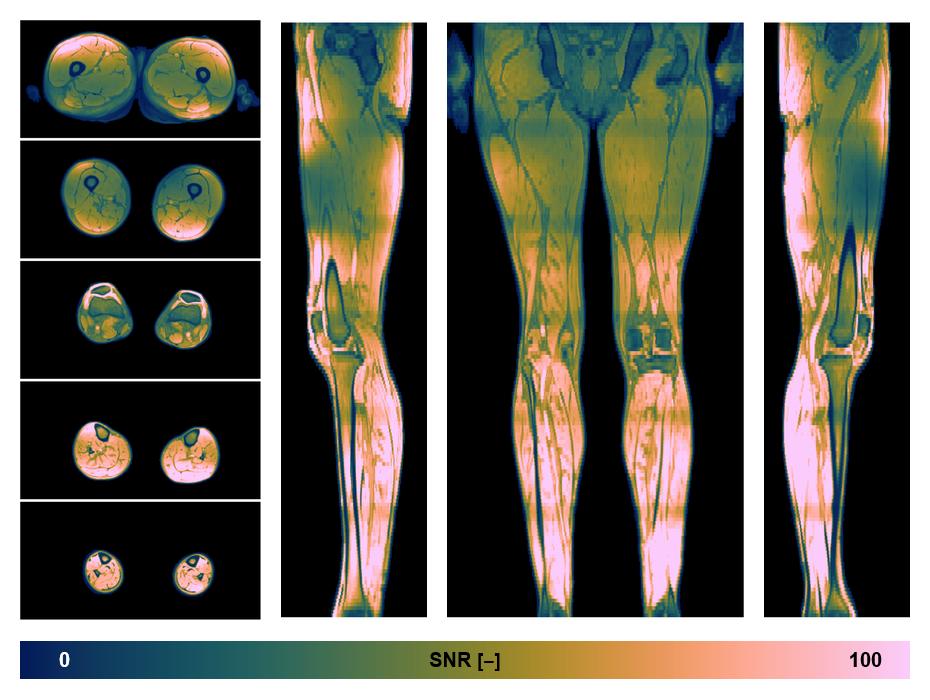

• SNR distribution

The SNR distribution of the dixon data.